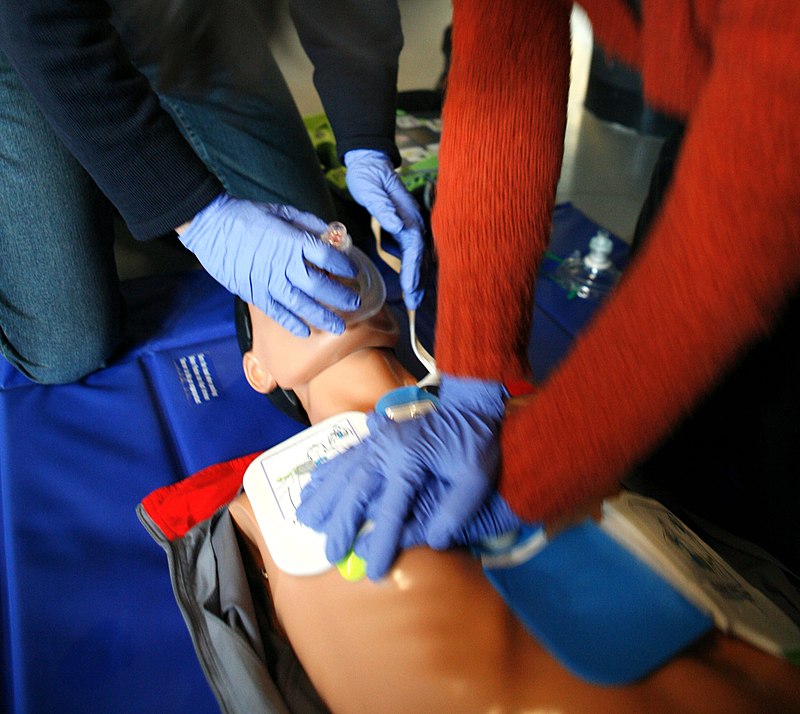

قیمت: 118٬000 تومان - دسته بندی فایل: پاورپوینتپاورپوینت احیای قلبی ریوی CPRCardio pulmanary Resusiation

فروش ویژه پاورپوینت حرفه ای یک با تخفیف استثنایی فقط 113588 هزار تومان تعداد اسلاید : 93 اسلاید